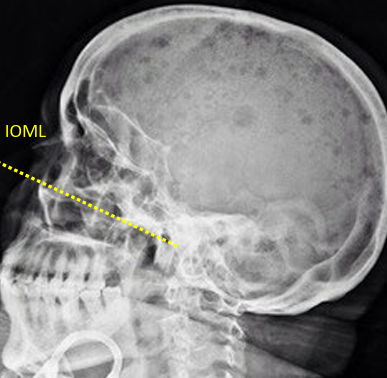

erect: true lat, IOML // LA of IR, IPL perp to IR